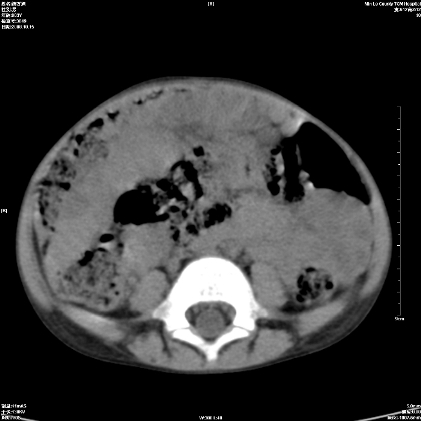

标题: PED1609:男性,3岁。彩超示肝Ca. [打印本页]

标题: PED1609:男性,3岁。彩超示肝Ca.

3岁;肝低密度灶;有钙化;有转移灶;考虑肝母细胞瘤;查afp

考虑神经母细胞瘤并肝转移

考虑:1、右侧后下纵隔畸胎瘤。

2、肝脏多发血管内皮细胞瘤。

建议:增强确诊。